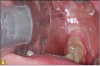

Giomer restoratives are bioactive regenerative materials that can be used where traditional direct composite materials are indicated. In the case presented in Figure 1, decay was noted on the occlusal surfaces of a first and second molar. What often looks like a very small amount of decay on the surface can lead to the discovery of significant dentin destruction. The quadrant was isolated and air abrasion was performed using 50 µm aluminum oxide (Figure 2). The occlusal groove enamel was abraded, revealing obvious decay to the dentin (Figure 3). Decay was identified with caries indicator and removed with a #2 round bur and slow-speed handpiece, with the goal of preserving as much healthy tooth structure as possible (Figure 4). Caries indicator stains denatured collagen and debris and helps to identify areas needing attention by the dentist, but equally importantly, it identifies areas without damage that can be preserved.

Fig 1. Subtle decay, occlusal view.

Figure 1